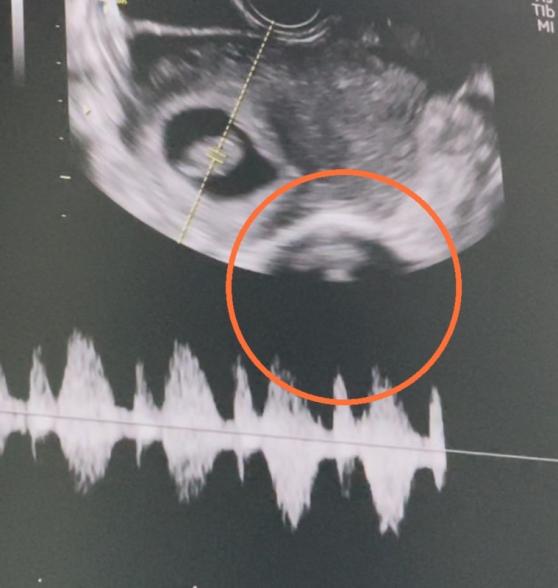

オレンジの丸の中はなんでしょうか?

先生は左に映っている子の心臓を確認するとあっさり診察を終えました。

この診察から数日して撮っていた動画に映っている事に気づきました。

次の診察まで何なのか毎日気になって仕方ありません。